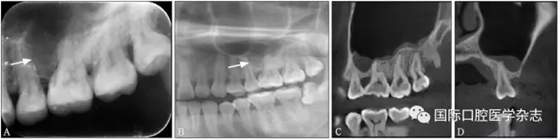

典型病例7 患者因左上后牙牙齦不適就診,X線片示26牙近中側(cè)大面積透射區(qū),邊界清楚。全景片示26牙根尖周圓形透射影,有致密骨白線包繞。CBCT的矢狀位和冠狀位圖像示為變異上頜竇(圖7)。

A:X線片;B:全景片;C~D:CBCT矢狀位和冠狀位圖像。

圖 7 變異上頜竇

Fig 7 Aberrant anatomicalvariation of maxillary sinus